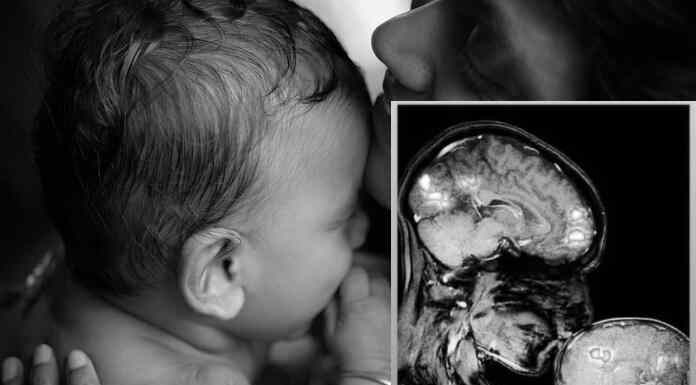

Αυτή η εικόνα είναι η αλληλεπικάλυψη της μαγνητικής που απαθανατίστηκε κατά τη...